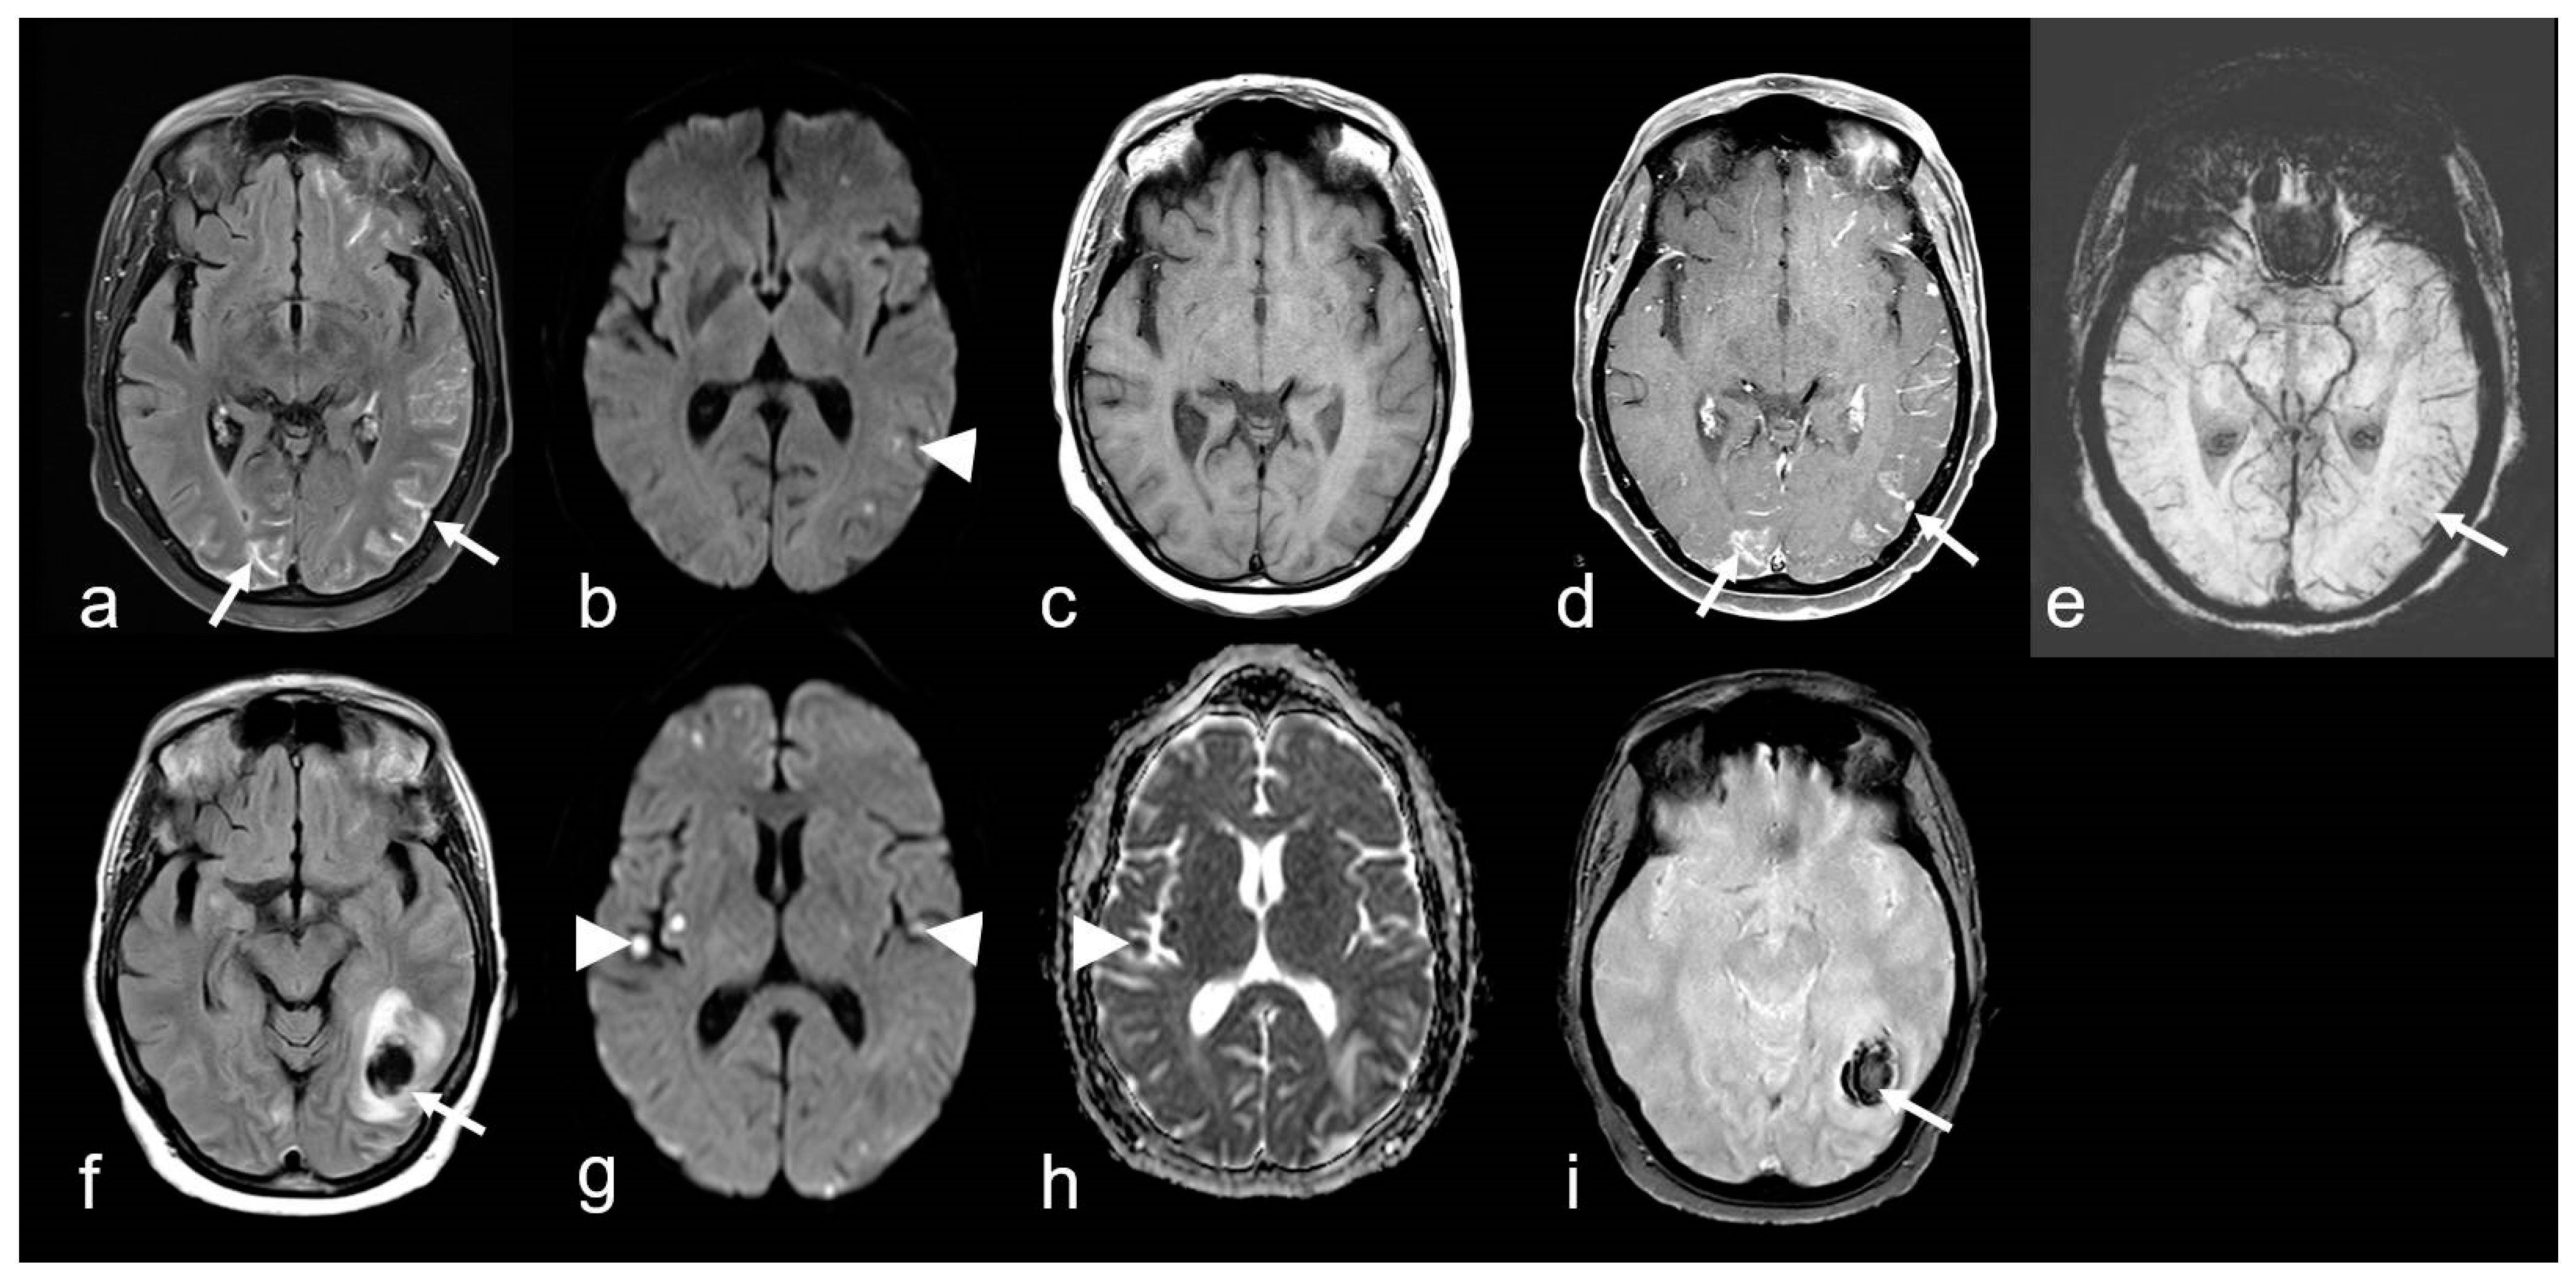

Figure 7.

A 68-year-old woman suffering from progressive dizziness and visual blurring for several weeks (upper row) and acute deterioration (lower row) due to cerebral amyloid angiopathy-related inflammation (CAA-ri) with associated vasculitis (amyloid-beta-related angiitis, ABRA). (a–e): Multifocal hyperintense sulcal effusions ((a), arrow; fluid-attenuated inversion recovery (FLAIR)), focal small lesions with restricted diffusion temporo-parietal left ((b), arrowhead; diffusion-weighted imaging (DWI, b = 1000 s/mm2)), distinct multifocal leptomeningeal enhancement ((d), arrow; (c,d): T1 WI before (c) and after (d) contrast agent application); (e): multiple microbleeds (arrow, susceptibility-weighted imaging (SWI)). (f–i): Subacute lobar intracerebral hemorrhage (ICH; (f), arrow); (g,h): new cortical / subcortical infarcts ((g,h): arrowhead; DWI, b = 1000 s/mm2, apparent diffusion coefficient (ADC) map); (g): T2* WI demonstrating inhomogeneous signal loss (arrow); MRI 1.5 T Intera, Philips Healthcare.

Histological examination revealed amyloid deposits, accompanied by lymphocytic infiltrations, either perivascular or within the vessel wall itself [97,99,105]. The latter feature has been categorized as Aß-associated vasculitis (ABRA) (Figure 7 and Figure 8) [108,109]. However, in more recent studies, no distinction has been made between these two variants [89]. Nevertheless, primary CNS angiitis (PCNSA) must be differentiated from ABRA due to the presence of inflammatory vessel wall infiltrates without amyloid deposits on histological examination [96,109,110,111,112,113].